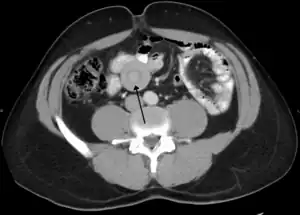

An intussusception is often suspected based on history and physical exam, including observation of Dance's sign. A digital rectal examination is particularly helpful in children, as part of the intussusceptum may be felt by the finger. A definite diagnosis often requires confirmation by diagnostic imaging modalities. Ultrasound is the imaging modality of choice for diagnosis and exclusion of intussusception, due to its high accuracy and lack of radiation. The appearance of target sign (also called "doughnut sign" on a sonograph, usually around 3 cm in diameter, confirms the diagnosis. The image seen on transverse sonography or computed tomography is that of a doughnut shape, created by the hyperechoic central core of bowel and mesentery surrounded by the hypoechoic outer edematous bowel.[11] In longitudinal imaging, intussusception resembles a sandwich.[11] It is also called "pseudokidney" sign because hyperechoic tubular centre is covered by a hypoechoic rim producing a kidney-like appearance.[12]